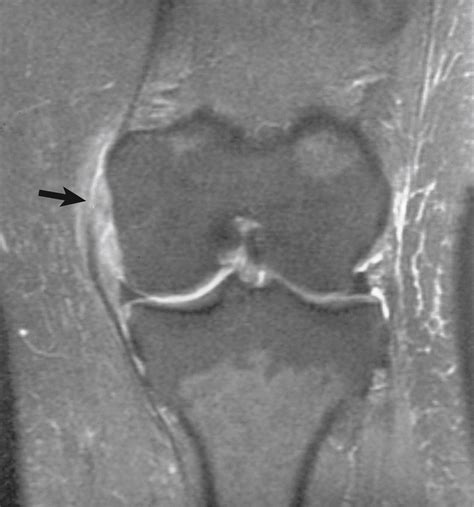

Advanced Imaging in Orthopaedics - Clinical Tree